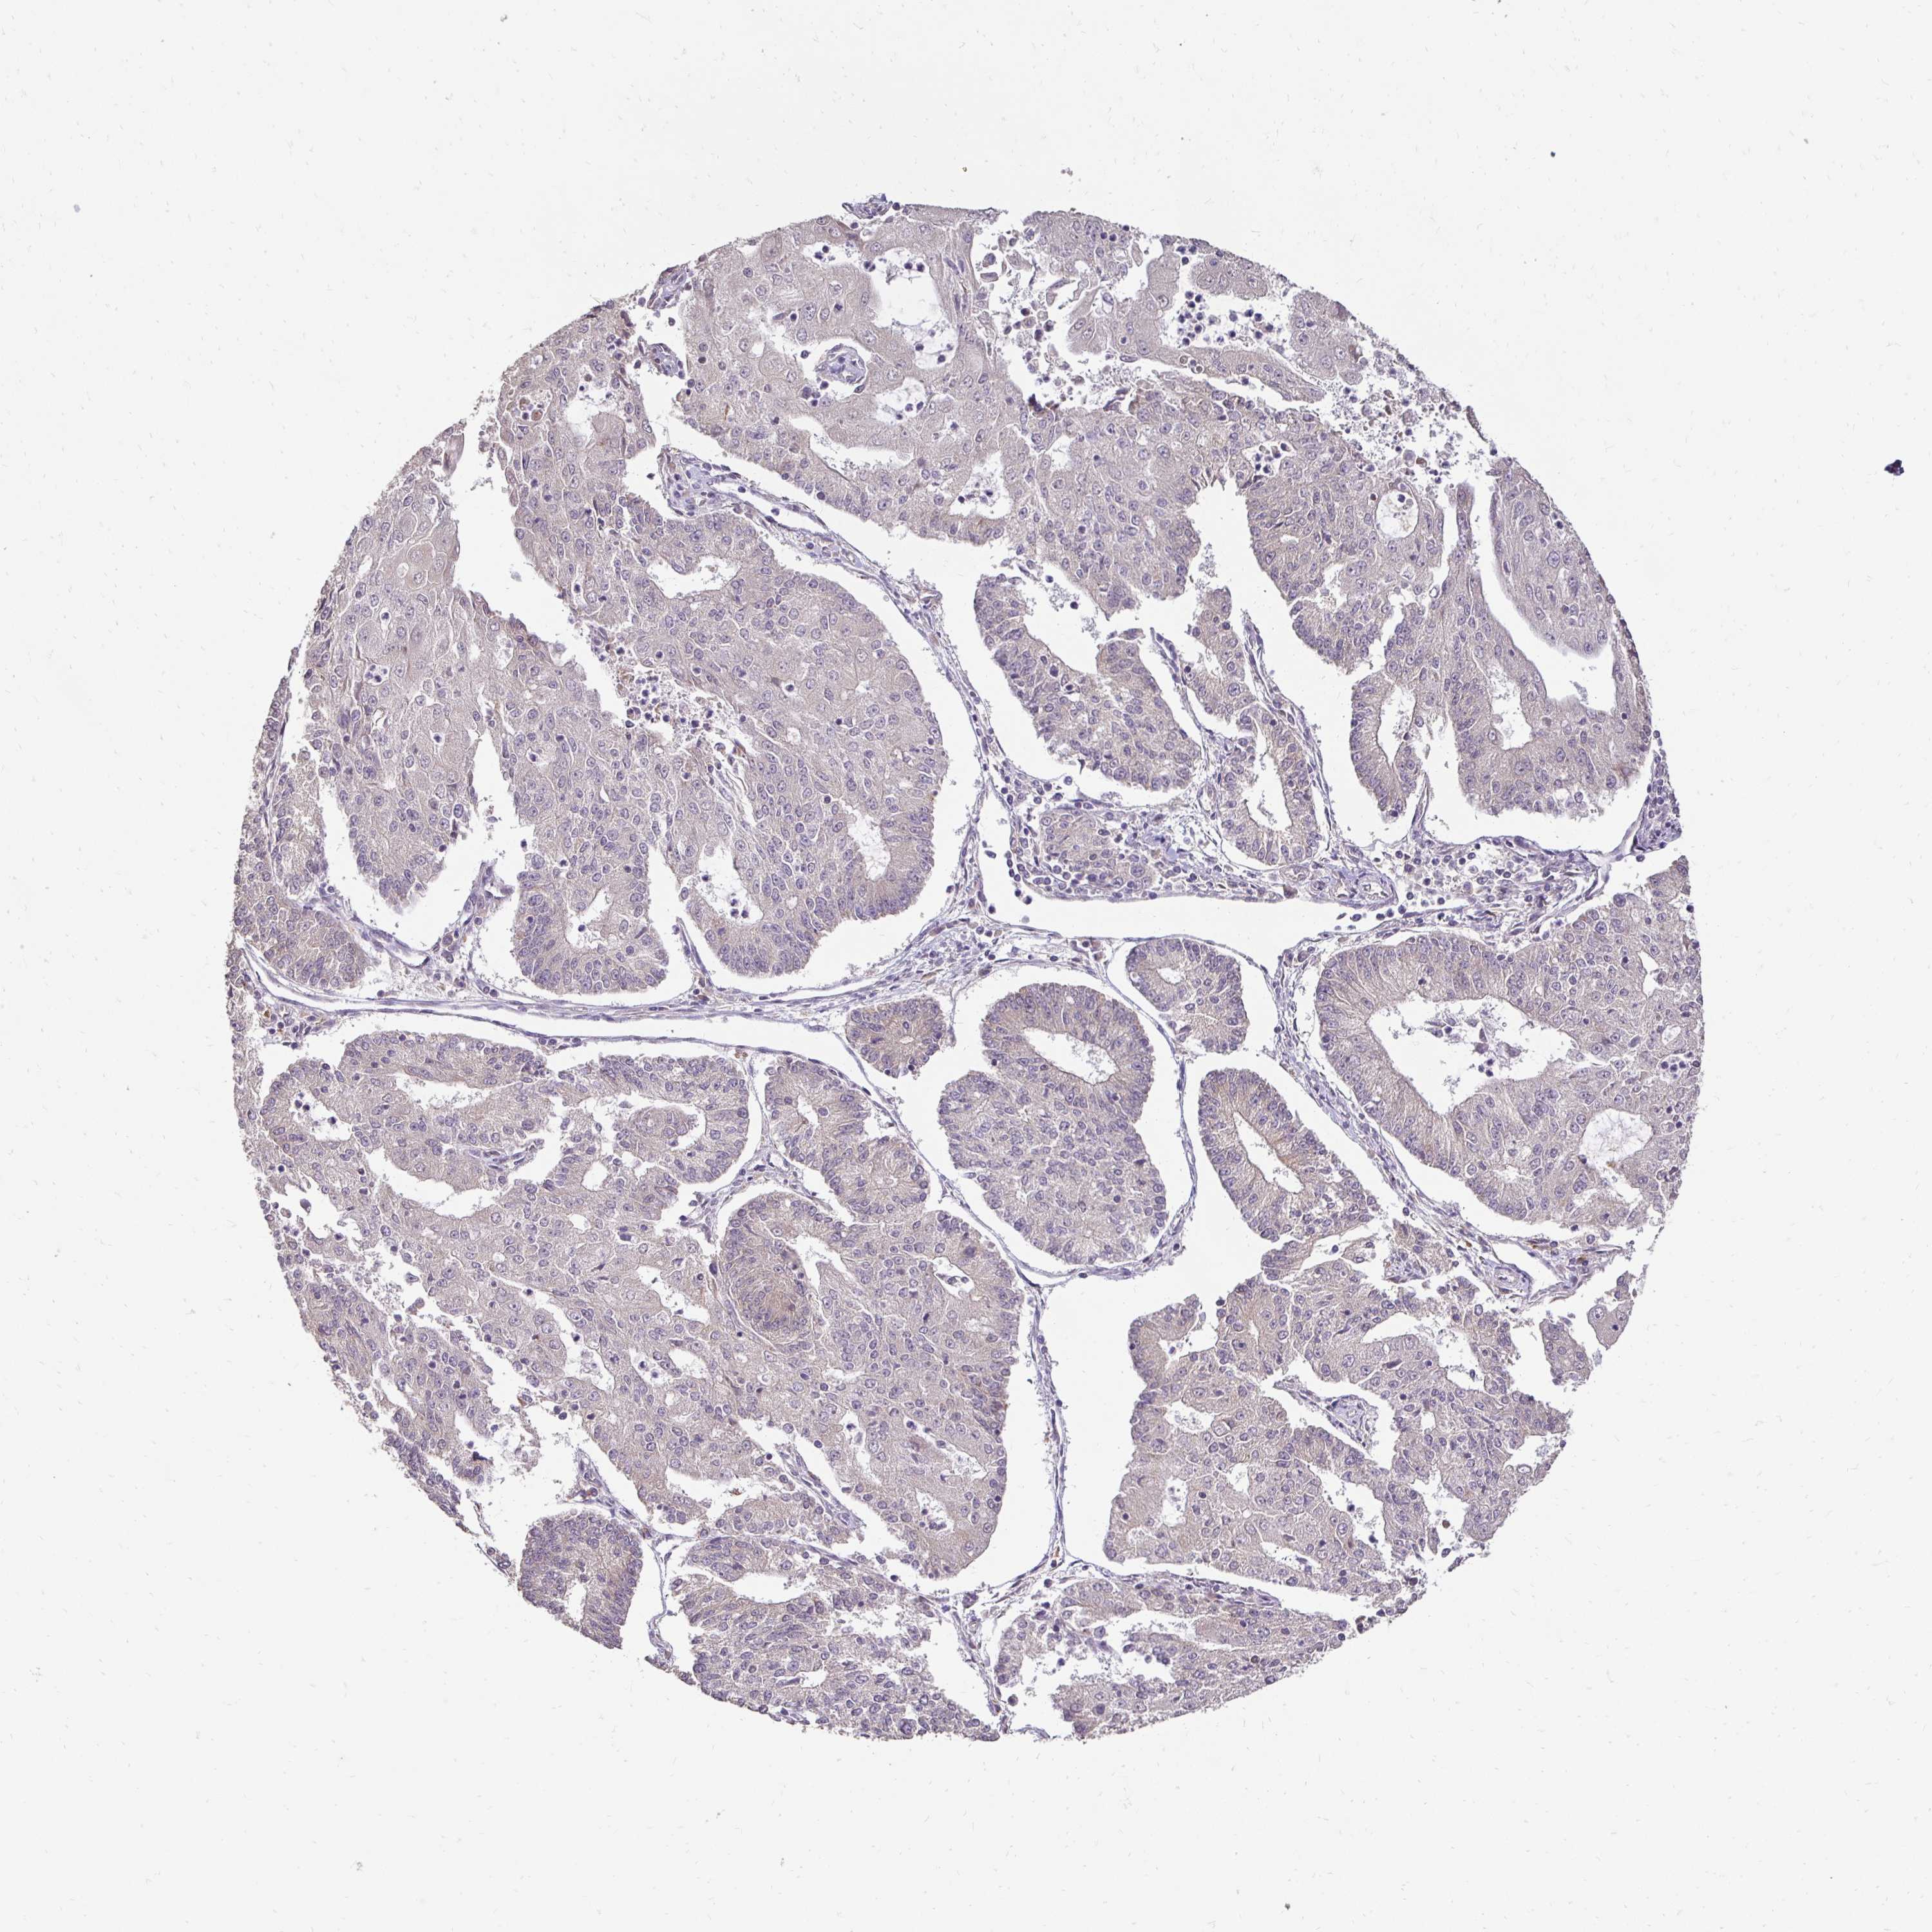

ENDOMETRIAL CANCER - Protein expressioni

A mouse-over function shows sample information and annotation data. Click on an image to view it in a full screen mode. Samples can be filtered based on level of antibody staining by selecting one or several of the following categories: high, medium, low and not detected. The assay and annotation is described here.

Note that samples used for immunohistochemistry by the Human Protein Atlas do not correspond to samples in the TCGA dataset.

Antibody stainingi

Antibody staining in the annotated cell types in the current human tissue is reported as not detected, low, medium, or high, based on conventional immunohistochemistry profiling in selected tissues. This score is based on the combination of the staining intensity and fraction of stained cells.

Each image is clickable and will lead to virtual microscopy that enables deeper exploration of all samples and also displays staining intensity scores, fraction scores and subcellular localization as well as patient and tissue information for each sample.

Antibody HPA053111

Antibody HPA061001

Staining

High

Medium

Low

Not detected

Intensity

Strong

Moderate

Weak

Negative

Quantity

>75%

75%-25%

<25%

None

Location

Nuclear

Cytoplasmic/membranous

Cytoplasmic/membranous,nuclear

Adenocarcinoma, NOS

Carcinoma, NOS

Adenocarcinoma, metastatic, NOS